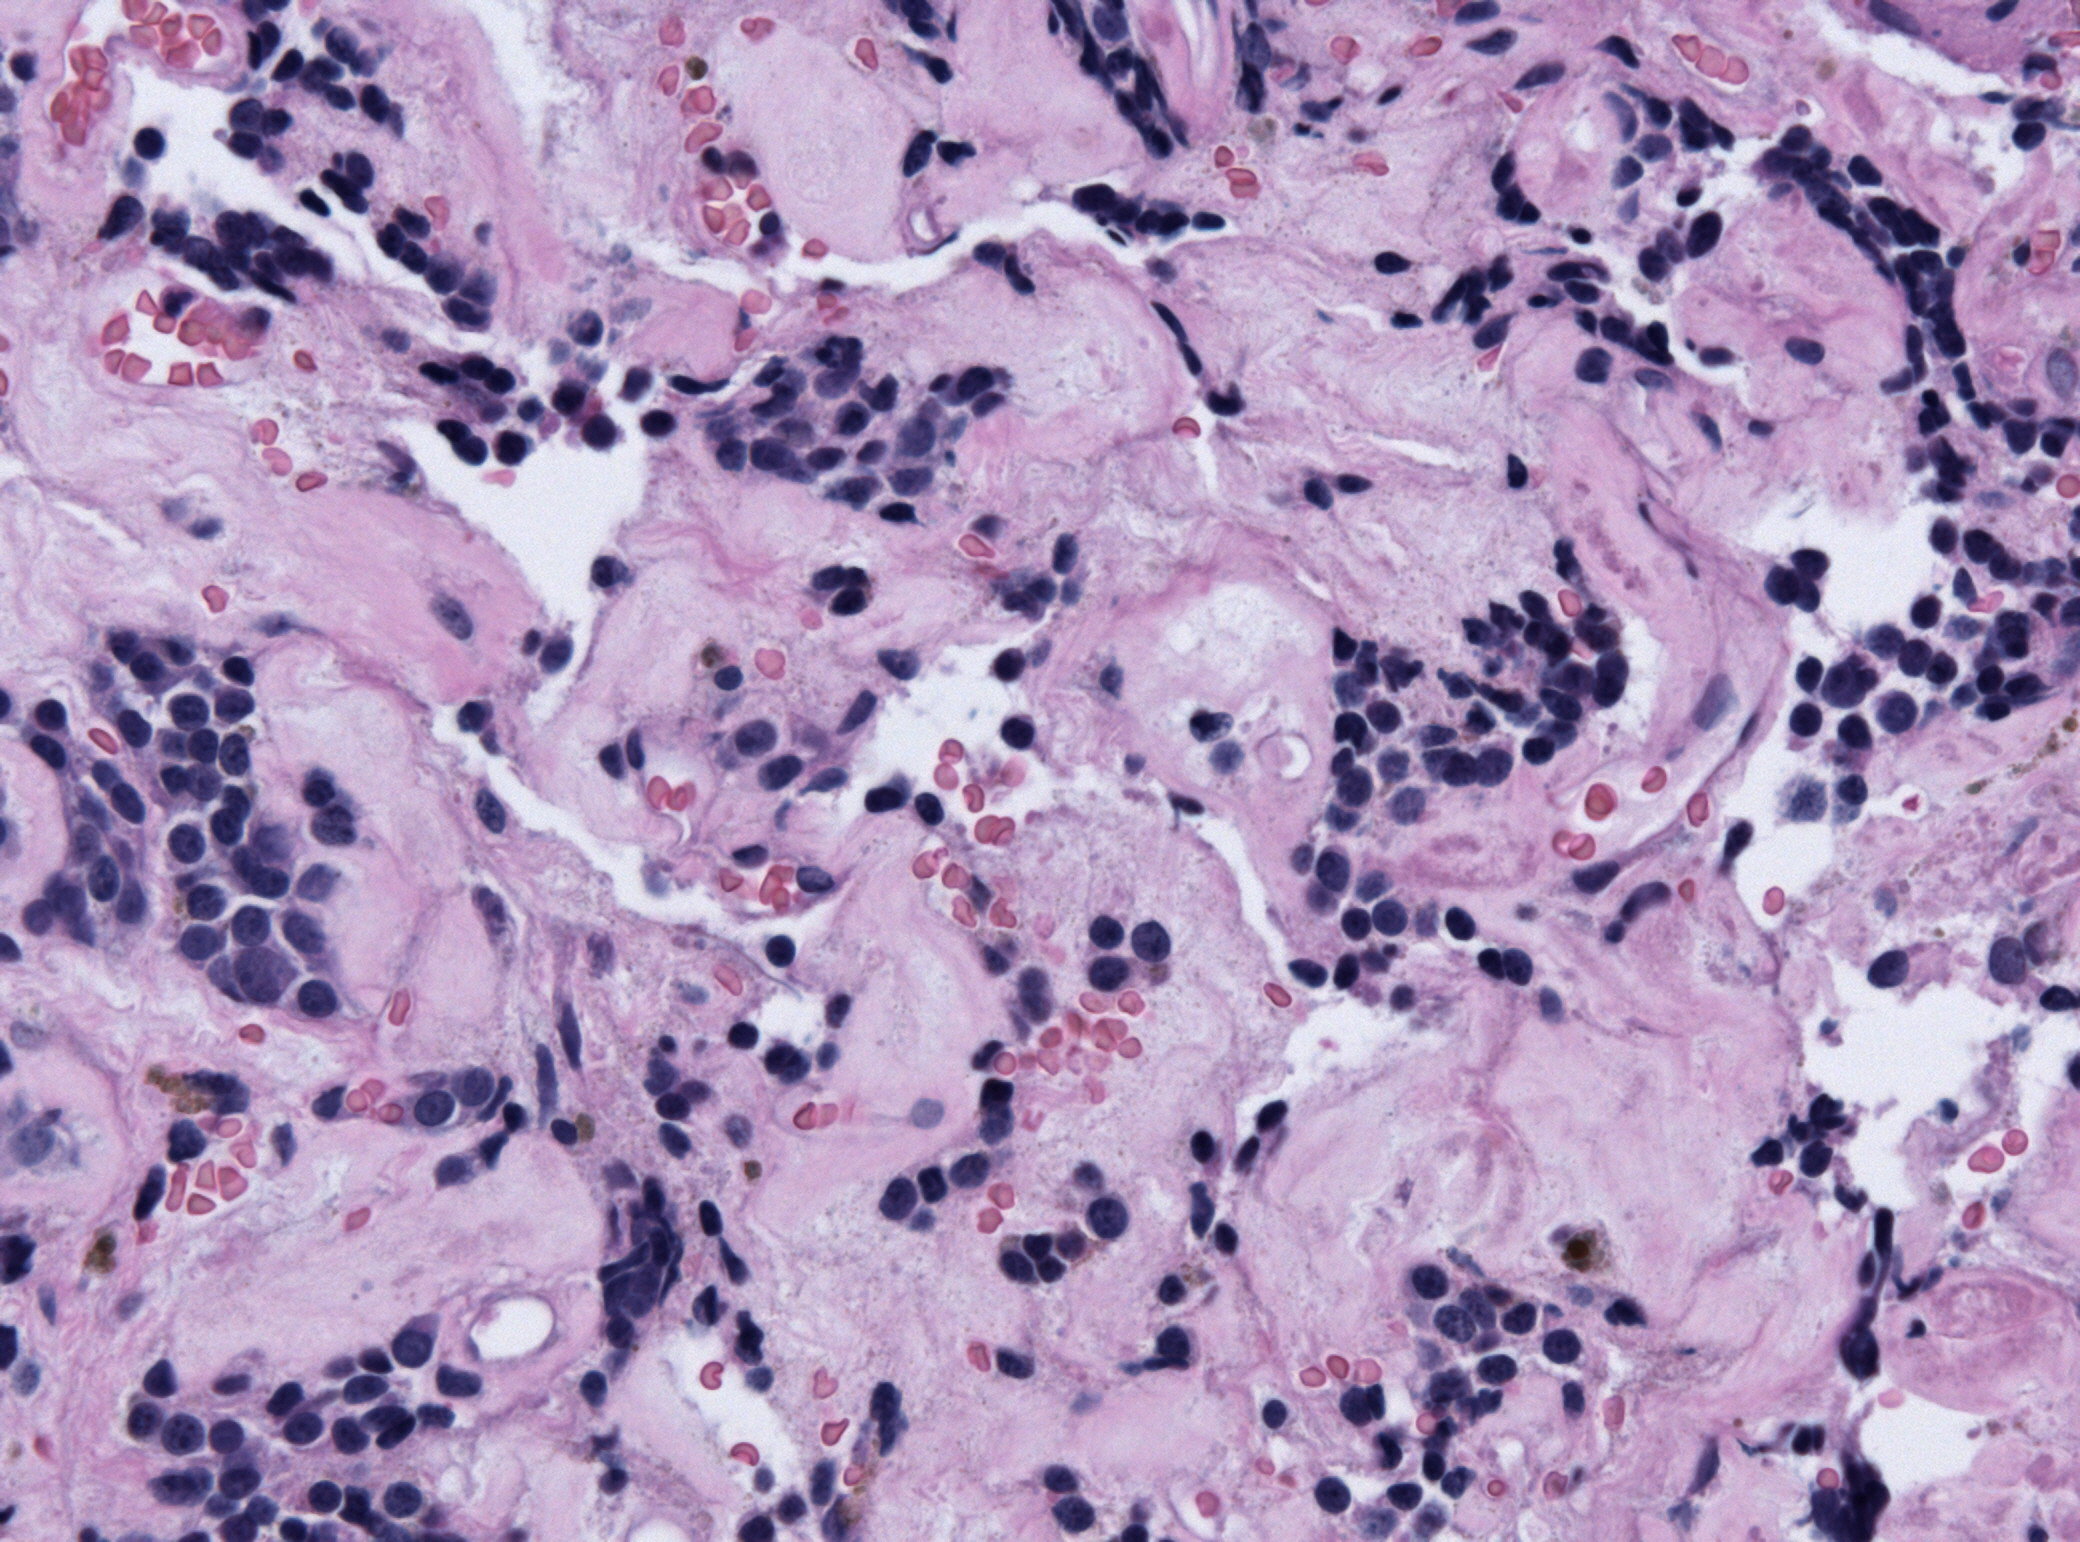

Плеоморфный рак

Плеоморфный рак 113 фото